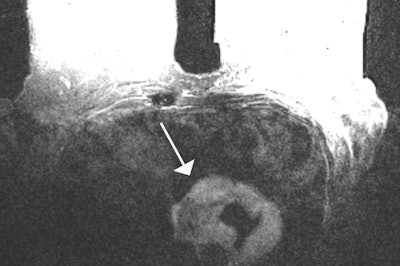

The MRI findings were compared with subsequent diagnostic procedures to differentiate malignant from benign lesions. The researchers detected 138 incidental findings in 107 of the 500 (21.4%) patients. The most common site was the liver (44.2%), followed by the lung (17.4%), mediastinum (15.9%), pleural cavity (10.9%), bone tissue (6.5%), spleen (2.2%), major pectoral muscle (2.2%), and kidney (0.7%).

Of the incidental findings, 18.1% were confirmed to be malignant. Malignant findings were exclusively detected in patients with known breast carcinoma, whereas incidental findings in patients without a history of carcinoma were all benign, according to Alduk and colleagues. Also, 24.8% of incidental findings among patients with history of breast cancer were malignant.

"Malignant lesions were exclusively detected in patients with previously known breast carcinoma, which emphasizes the importance of careful assessment of incidental findings in this group," the researchers added. "The present study showed that the prevalence of malignant findings in patients with a history of breast cancer is dependent on location, with the high likelihood of bone lesions being malignant (100%) in comparison to other locations."

Bone lesions are more likely to be malignant in comparison with other locations, probably because of the wide spectrum of benign abnormalities encountered in the liver (cysts and hemangiomas) or pleural cavity (effusions). Thus, a new bone lesion in a patient with breast carcinoma should be considered malignant until proved otherwise and should prompt further diagnostic workup. Also, 11.6% of hepatic lesions were metastatic, altering further treatment, so indeterminate lesions that do not satisfy the criteria for cysts or hemangiomas require further diagnostic workup (using ultrasound, CT, or liver MRI).